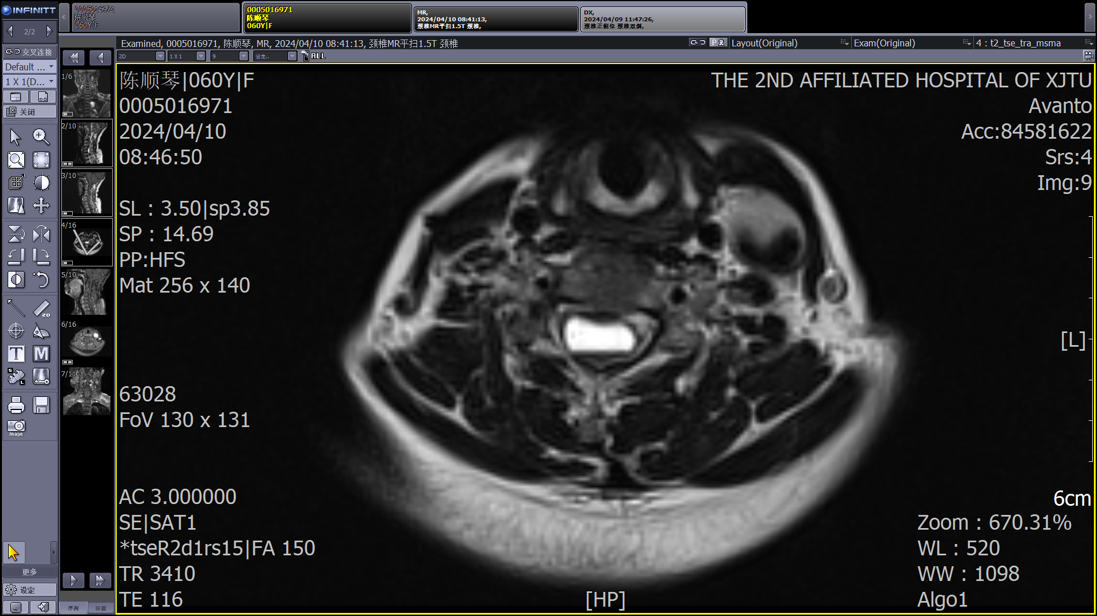

患者为一名中年女性,因颈部疼痛和四肢麻木症状就医,颈椎MRI检查结果显示颈4-7椎管内存在异常信号。由于病变位于颈段脊髓,手术风险极高,稍有不慎就可能导致瘫痪,多家医院的医生都遗憾地表示没有能力“接招”。